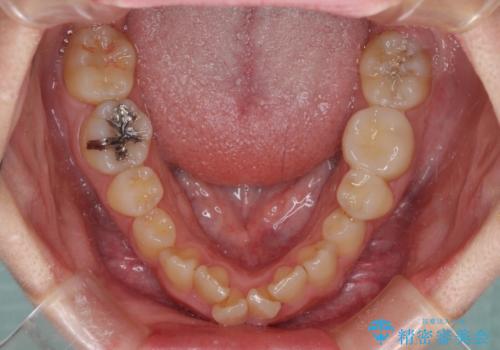

- 前歯のデコボコを気にして来院された患者様です。

上下の前歯にデコボコがあり、更にはディープバイトにより下顎前歯の大半が隠れている状態でした。

上顎左右第一小臼歯の2本を抜歯し、ワイヤー装置を使用して咬み合わせ高さを改善しながら、歯列を整えて行くこととしました。